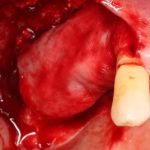

Поэтому после удаления зуба мы ждём, в общей сложности, около 4-8 недель, затем приступаем к имплантологическому лечению. Хотя, иногда бывают ситуации, когда мы делаем синуслифтинг одномоментно с удалением зуба, а сам имплантат ставим попозже:

через 4 месяца: